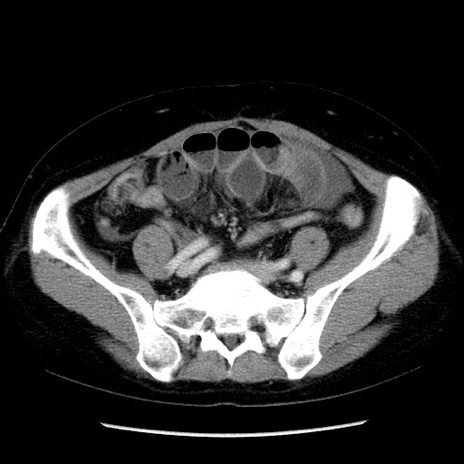

冠状断像